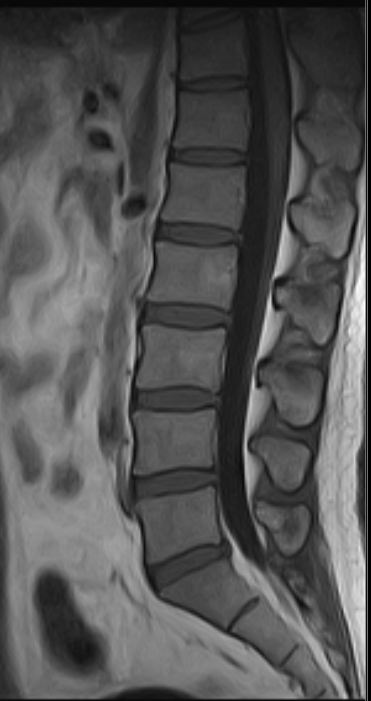

Spine | Spinal fractures, spinal instability, bone lesions | Spinal cord tumors, disc herniation, nerve root compression, inflammatory conditions |

Abdomen & Pelvis | Acute abdomen (appendicitis, intestinal obstruction), abdominal trauma, kidney stones | Liver tumors, pancreatic lesions, gynecological disorders (uterus/ovaries), prostate diseases |